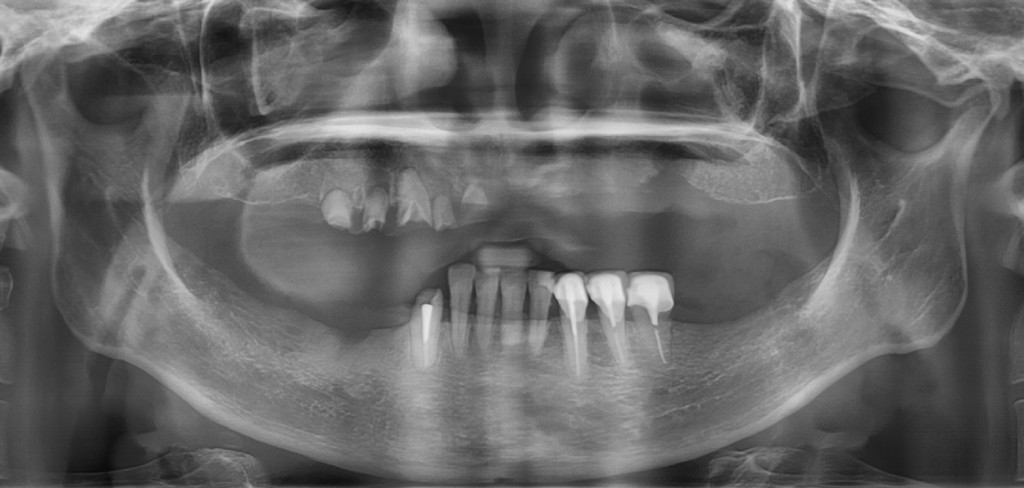

上顎長期缺牙,只剩幾個殘存牙根

殘根拔除後,植入6支人工牙根